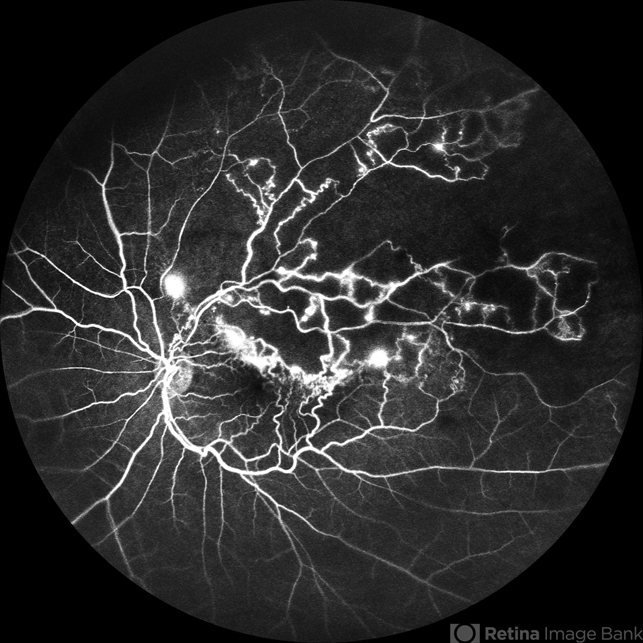

- branch retinal vein occlusion (BRVO), FLUORESCEIN ANGIOGRAPHY, fluorescein leakage, CNP areas, macular edema

- Fluorescein angiogram of a 52 year old man showing capillary non perfusion areas and leakages along the superotemporal arcade and at the macula.